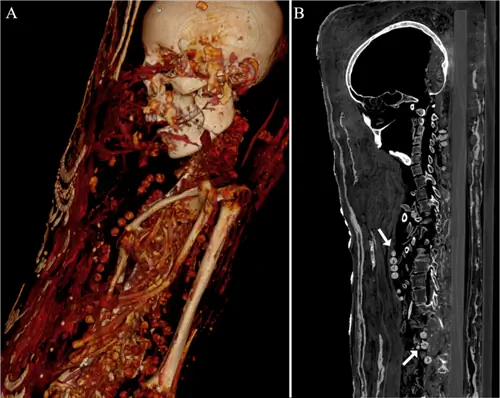

Три отсканированные мумии являются единственными известными примерами «портретных мумий, покрытых лепниной».«В отличие от того, чтобы быть похороненными в гробу, эти трое были помещены на деревянные доски, а затем завернуты в ткань и саван. Затем их украсили гипсом, золотом и портретом в полный рост, показывающим, как они выглядели, как укладывали волосы и что носили в жизни. Все трое когда-то были похоронены в Саккаре, большом некрополе к югу от Гизы.

Компьютерная томография показывает, что мужчине было от 25 до 30 лет, когда он умер, и что у него было несколько полостей и непрорезавшиеся зубы. Его рост был всего 164 см (около 5 футов 4 дюймов). Несколько его костей сломаны, хотя считается, что это результат небрежного обращения того, кто обнаружил останки.

Самое любопытное, нет никаких доказательств того, что его мозг был удален во время процесса мумификации, как это было принято в других случаях. Также кажется, что для его сохранения использовалось мало химикатов для бальзамирования. Это говорит о том, что его просто завернули, покрасили и похоронили, и именно обезвоживание помогло сохранить его труп в такой хорошей сохранности.

Женщине было от 30 до 40 лет, ее рост составлял 151 см (4 фута 9 дюймов). У нее есть признаки артрита в коленях. Как и многие другие египтянки, она была похоронена в изысканных украшениях. На скане появилось несколько ожерелий, что свидетельствовало о том, что она была в достатке. По неизвестным причинам в ее животе также были обнаружены гвозди. Как и у ее коллеги-мужчины, ее мозг не был удален во время мумификации.

Последняя мумия принадлежала девочке позднего подросткового возраста. У нее были признаки доброкачественной опухоли на спине, и все ее внутренние органы были целы. В ее гробу есть шпильки, что говорит о том, что она носила волосы так, как изображено на ее портрете.